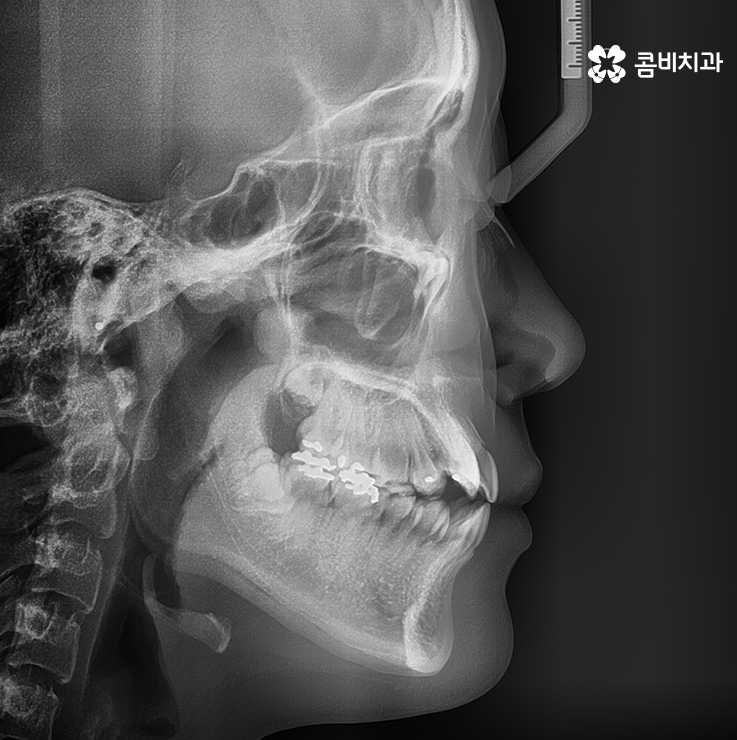

송곳니 덧니 치료를 할 때 주의해야 할 점은

자신의 골격과 얼굴형을 충분히 생각해야 한다는 것입니다.

덧니 자체만 본다면 비교적 심하지 않은 분들도

계실 수 있겠지만 치아가 돌출되어 있으신 경우에는

옆모습이 돌출입으로 보일 수 있기 때문에

앞모습과 옆모습, 전체 얼굴형을 고려하여

자신의 얼굴과 자연스럽게 어울리는 결과가 중요합니다.